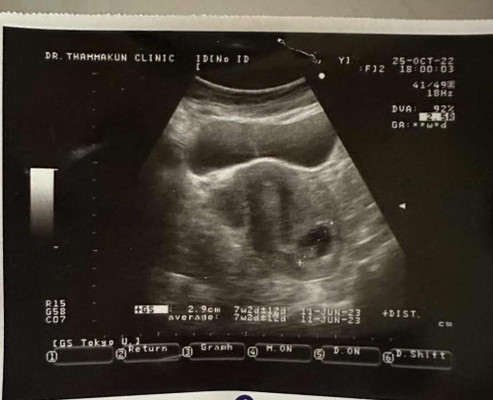

มีแม่ๆ คนไหนน้องอยู่ต่ำแบบนี้บ้างคะ ตอนนี้กังวลมากเลยค่ะ นับจากประจำเดือนน้อง8w6d ในใบอัลตร้าซาวน์ น้อง7w2d ค่ะ